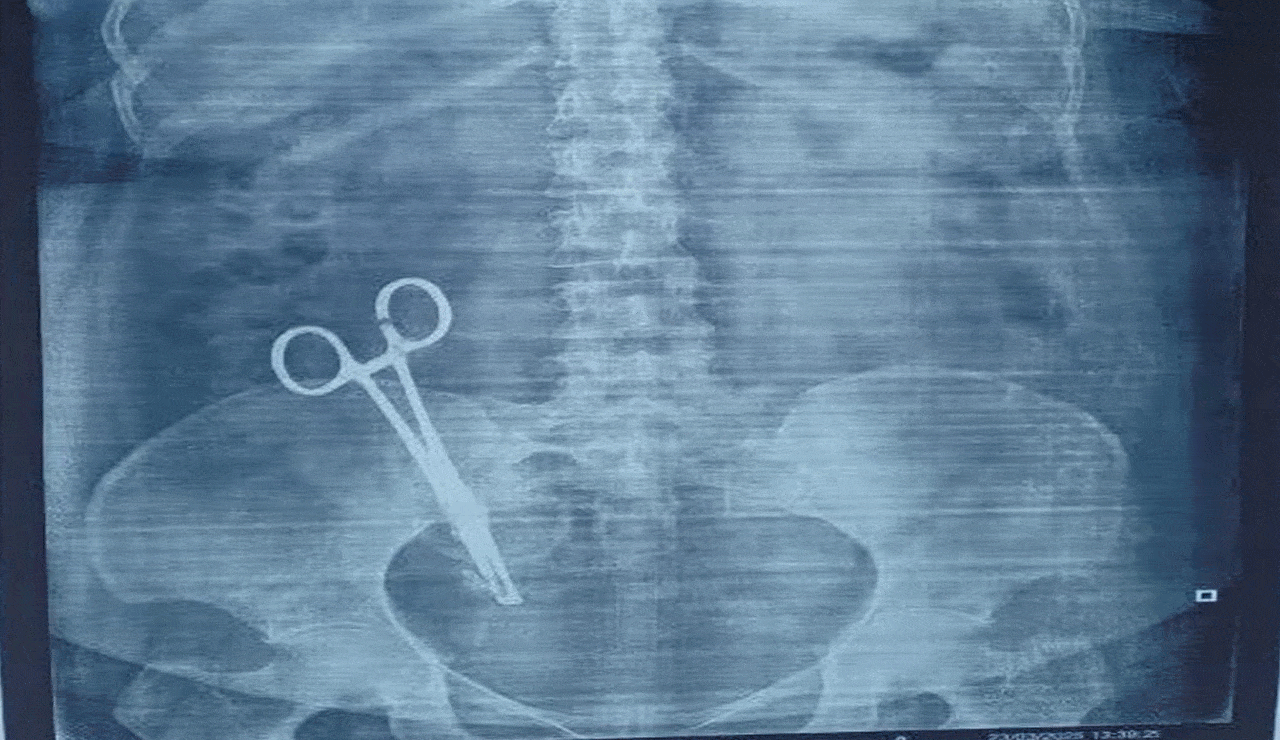

Viral: Woman Suffers from Stomach Pain for 17 Years, X-Ray Reveals Shocking Truth

According to Arvind, his wife underwent a cesarean section performed by Dr. Pushpa Jaiswal nearly two decades ago. The recent medical reports have now revealed alleged negligence during that surgery, prompting the family to seek legal action.

“We have suffered silently for 17 years without knowing the real cause of my wife’s condition. Now that we have the evidence, we want justice,” Arvind said.